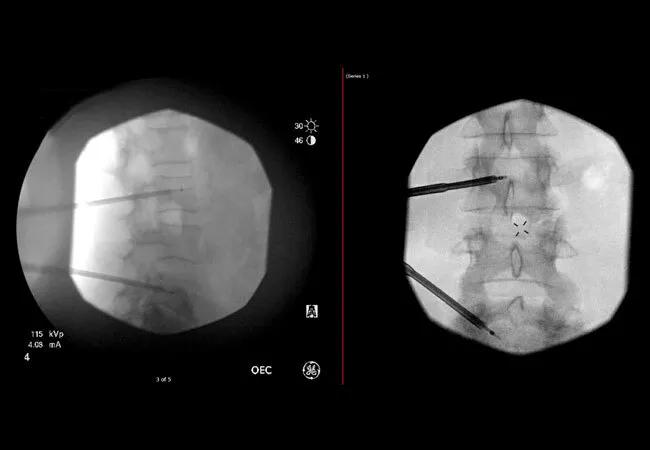

Antero-posterior and lateral images of cooled radiofrequency ablation and cementoplasty of spinal metastases after pulling out the instruments.

Dr. Neale referred her to Sherif Costandi, MD, an interventional pain management specialist, for more effective treatment options. Lytic lesions had infiltrated her spine at L3 and L5. Dr. Costandi treated her with cooled radiofrequency ablation therapy (cRFA) to the affected vertebrae coupled with cementoplasty to stabilize the area using the same bone access channel. “She had been in pain for about six months, and our best noninterventional efforts hadn’t worked,” says Dr. Costandi. “We were able to drop her pain from an 8 or 9 out of 10 to a zero and improve her quality of life dramatically.”